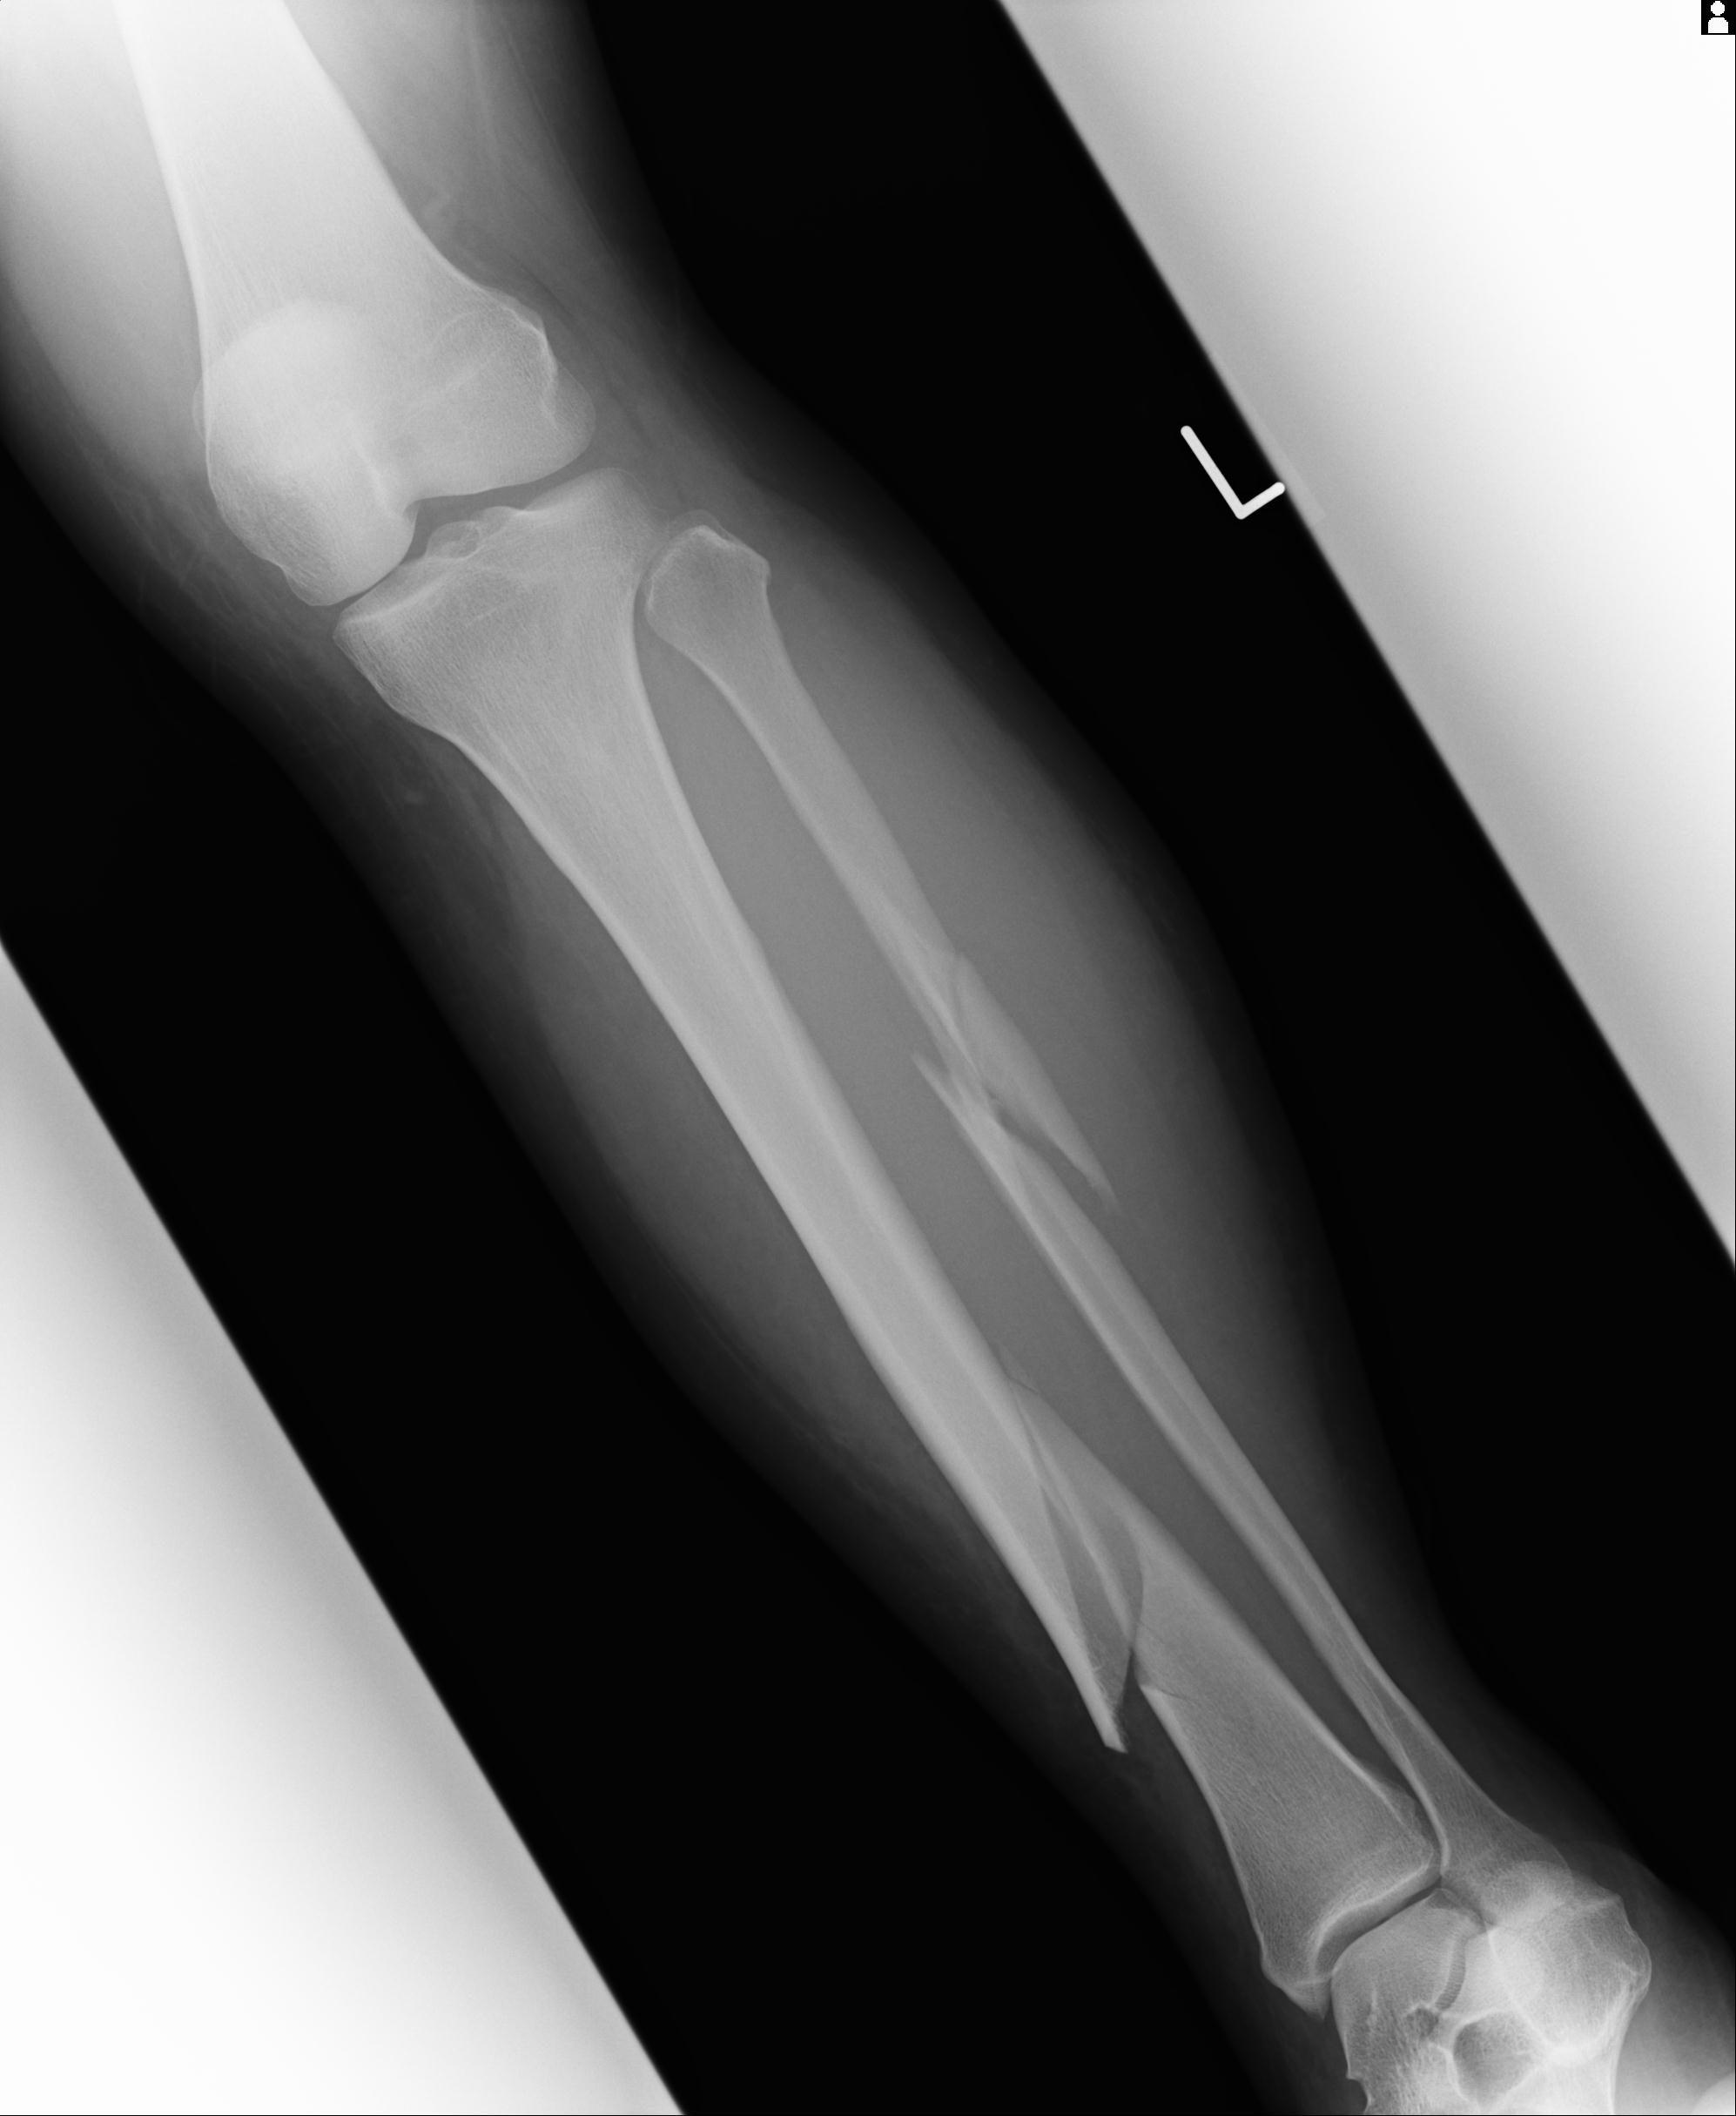

110211 1/6 1/8 左前腕 4R 15歳男性 橈骨骨幹部骨折